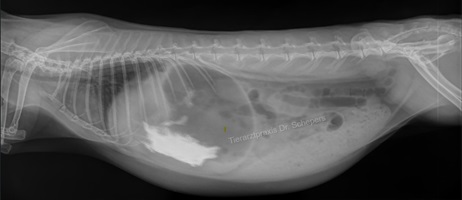

Röntgendiagnostik

Die sichere Diagnose wird durch ein Röntgenaufnahmen gestellt; hierdurch kann die Konsistenz des Mageninhalts (fest, flüssig, aufgegast) auch von weniger geübten Tierärzten sicher und objektiv beurteilt werden. Zudem besteht eine objektive Vergleichsmöglichkeit für spätere Verlaufskontrollen.

Weiterhin kann objektiv beurteilt werden, wie groß der Magen tatsächlich ist, wie lange der Zustand bereits besteht (beim mechanischen Ileus v. a. anhand der Konsistenz des Mageninhaltes: anfangs homogen, anschließend "spiegeleiartig" durch beginnende Gasbildung) sowie inwieweit eine Magentympanie (= Aufgasung) beteiligt ist. Ein gewöhnlicher Kaninchenmagen ist rund, mit homogenem, strukturiertem Inhalt gefüllt und ragt maximal zu einem Drittel über den Rippenbogen hinaus.

Auch kann die Füllung des Magen-Darm-Trakts bereits einen deutlichen Hinweis auf einen Darmverschluss liefern: Bei dem typischen, im vorderen Dünndarmbereich lokalisierten Verschluss ist die Darmschlinge unmittelbar hinter dem Magenausgang leer und luftgefüllt, der dahinter befindliche Darm hingegen noch futtergefüllt.

Sitzt der Verschluss in einem anderen Darmabschnitt, kann der Darm zu größeren Anteilen mit Luft gefüllt sein oder gefüllte, stark dilatierte (= überdehnte) Areale aufweisen. In letzterem Fall kann der Magen (noch) eine normale Größe besitzen, da sich der Futterbrei zunächst im Dünndarm und erst später bis in den Magen zurückstaut.